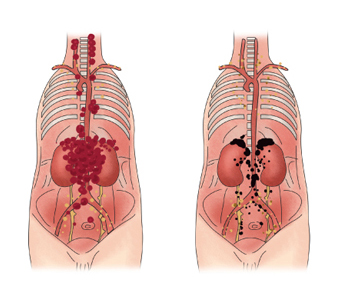

신경 특이 에놀라제는 신경내분비세포로 혈소판, 적혈구, 림프구 등에 분포하고 있습니다. NSE는 정상적으로 혈액 내 소량 존재하지만 신경아세포종과 폐세포암일 경우 증가될 수 있습니다. NSE 수치는 조기암에서 양성률일 경우가 적기 때문에 선별검사보다는 치료 효과의 판정이나 경과 관찰, 재발 유무를 모니링하기 위해 사용됩니다.